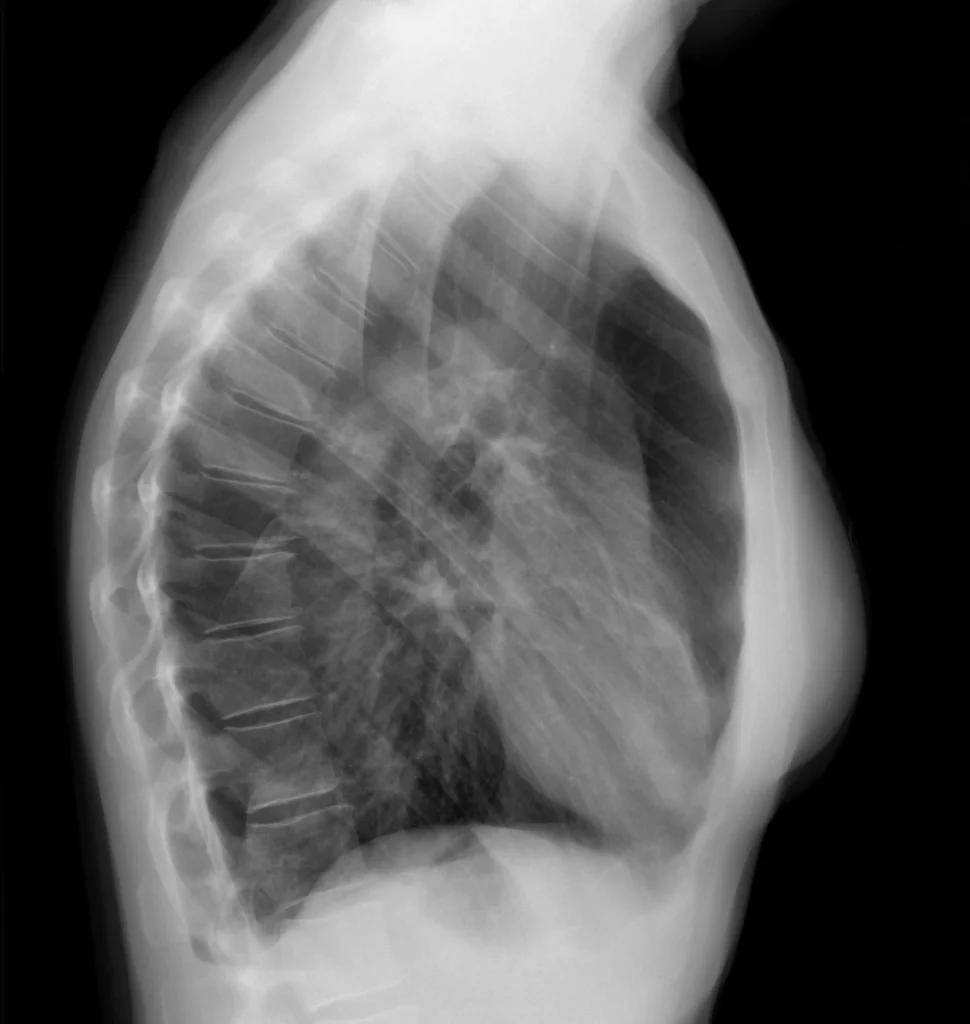

Radiología

Rx de tórax LL. No es absolutamente necesaria para el diagnóstico y la caracterización del neumotórax. En está paciente se puede observar la hipertransparencia en el espacio retroesternal, y posterosuperior, proyectado por fuera de la aorta.